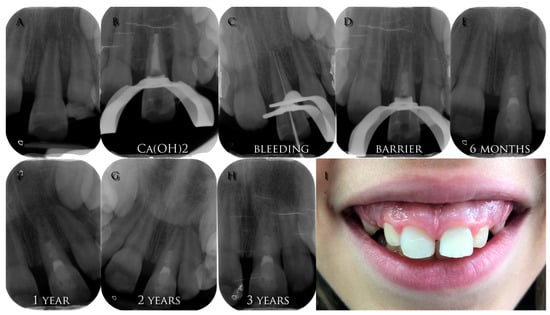

The AAE developed the “Clinical Considerations for a Regenerative Procedure”, as the guidelines to follow regarding this topic [,]. The ESE also published its position statement about revitalization procedures with clinical guidelines []. Both documents contain structured and evidence-based instructions for clinical procedures (Figure 3), which are summarized in the Scheme 1.

Figure 3.

(A) Pre-operative radiograph of a young necrotic upper left central incisor with open apex and a periapical lesion; (B) radiograph of the calcium hydroxide medication; (C) working length radiograph of the file inducing bleeding; (D) radiograph of the coronal barrier positioned; (E) 6-months control radiograph; (F) 1-year control radiograph; (G) 2-years control radiograph; (H) 3-years control radiograph; (I) 3-years clinical image.